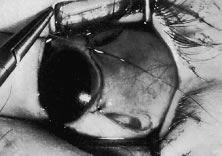

A muscle that moves from its desired location is called a slipped muscle.43–46 Causes of a slipped muscle include untying of the knot (Fig. 77A and B), inadvertent cutting of the suture, placing the suture too close to the insertion, or taking an inadequate bite of sclera with passage of the needle. In the latter case, the suture will “cheese wire,” or pull through the sclera. Finally, if the suture engages only the muscle capsule and not the tendon, the tendon can slide posterior within the muscle capsule. Because the maximal pull, or force, generated by an extraocular muscle is only 50 g, insufficient strength of the suture material is seldom the cause of a slipped muscle.

Fig. 77. A. This patient had a lateral rectus muscle recessed 5 days ago. The patient was referred for evaluation of overcorrection and poor abduction. The incision was explored, and the suture that was holding the rectus muscle had become untied. Careful examination of the blue suture under the conjunctiva raised suspicion of this complication. B. Schematic demonstrating the findings at surgical correction.